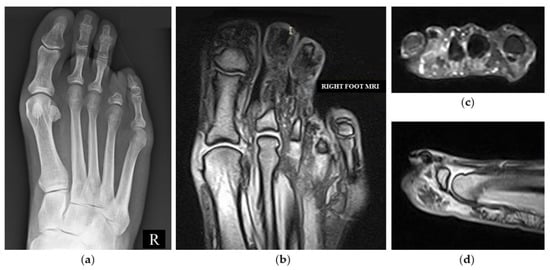

2. Case Presentation